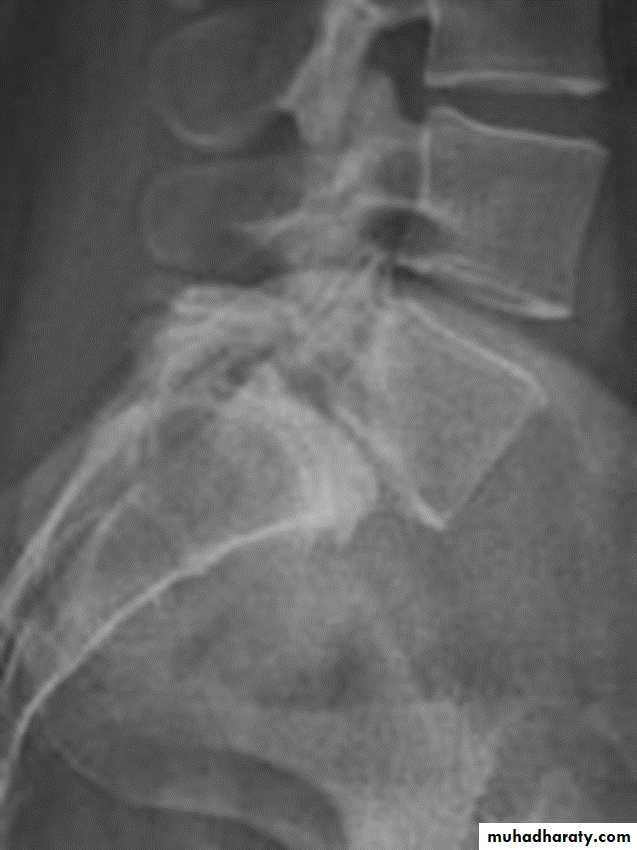

Spondylolysis and spondylolisthesis

Spondylolisthesis: is a term denoting fore ward or backward movement of a vertebra relative to the vertebral segment below, typically due to spondylolysis (pars interarticularis defects) .Spondylolysis: Spondylolysis is a defect in the pars interarticularis of the neural arch, the portion of the neural arch that connects the superior and inferior articular facet in which cause defect in the neck of scotty dog .

scotty dog sign refers to the normal appearance of the lumbar spine when seen on oblique radiographic projection. On oblique views, the posterior elements of vertebra form the figure of a Scotty dog with:

the transverse process being the nose

the pedicle forming the eye

the inferior articular facet being the front leg

the superior articular facet representing the ear

the pars interarticularis (the portion of the lamina that lies between the facets) equivalent to the neck of the dog.